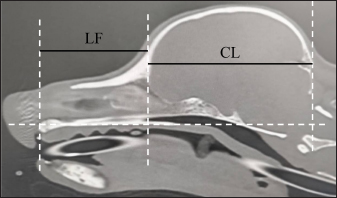

where length of the facial skull (LF) is the length between the nasion and the cranial edge of the olfactory bulb horizontal to the hard plate and cranial length (CL) is the length between the cranial edge of the olfactory bulb and inion horizontal to the hard plate (Fig. 3).

Fig. 3. CT measurements for Sct-Index (sagittal section). LF: the length between the nasion and the cranial edge of the olfactory bulb horizontal to the hard plate. CL: the length between the cranial edge of the olfactory bulb and the inion horizontal to the hard plate. Window width: 5,000, window level: 1,000.